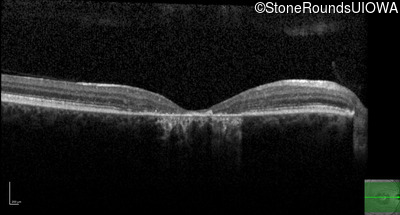

AR Stargardt Disease (IIA)

Age at visit:

45 years

OD

OS

20/200 -2 sc

OCT Stack

AR Stargardt Disease

ABCA4

Val1854Leu GTG>TTG

Gly1961Glu GGA>GAA

AR